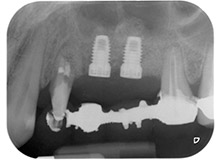

Mujer de 58 años de edad, que además es una apreciada colega y amiga, y se quejaba de dolor y de un aumento en la movilidad del pilar del puente de la pieza dental 24. También había inflamación periodontal, con bolsas de una profundidad de 7 mm en sentido mesiobucal y más de 12 mm en sentido distal, así como furcación de tercer grado. Asimismo, la radiografía reveló una lesión periodontal extensa alrededor de la región apical de la pieza dental 24 (figura 1) tratada previamente con endodoncia (alio loco).

Un mes después, en el día de la intervención, el dolor y la inflamación se habían reducido al mínimo en la pieza 24, pero seguía habiendo una movilidad de clase II de Miller. Después de la apertura de los colgajos y de la limpieza del tejido infectado periapical y perirradicular, la extensión del defecto óseo quedó evidente (figuras 2 y 3).

En la raíz bucal, faltaba todo el hueso vestibular y distal. Básicamente, la fijación se limitó a la raíz palatal, lo que corroboró el mal pronóstico preliminar. La pieza 27 también mostró una fijación horizontal reducida (figura 12) y una rarefacción apical mínima (figura 1), si bien sin síntomas clínicos.